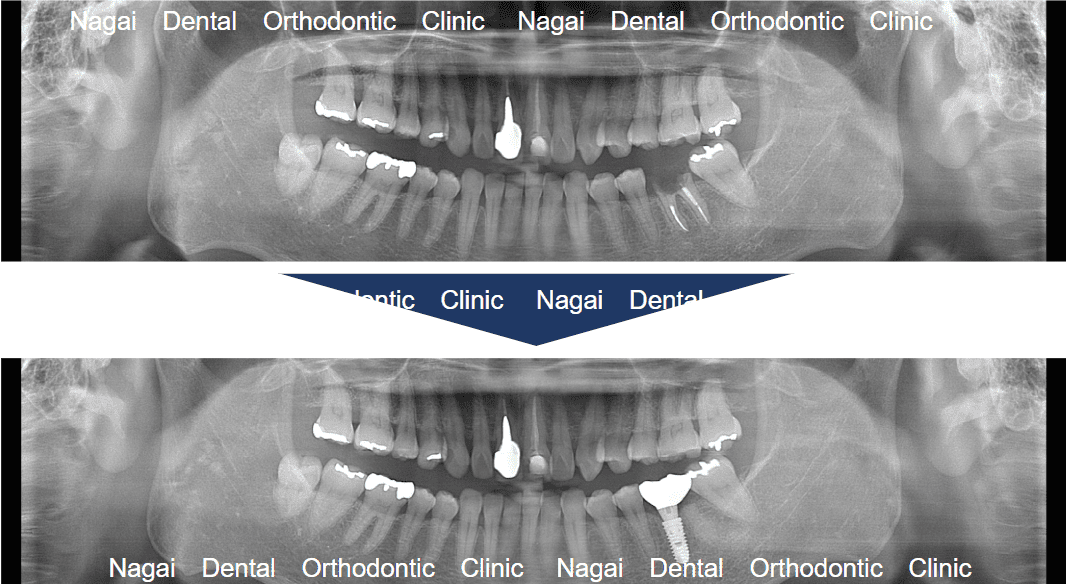

【口腔内の詳細変化】

▲再構築を目的とした治療を行いました

▲支持の安定が期待される治療を行いました

| 治療内容 | 左下顎:インプラント1本 |

|---|---|

| 年齢/性別 | 50代/女性 |

| 背景 | 被せ物の脱離で来院されましたが、精密検査にて保存困難な歯根破折が判明。周囲の健康な歯を削らずに済むインプラント治療を選択し、約4か月で天然歯のような美しさと噛み心地の回復を図りました。審美・機能ともに改善が認められ、再び自信を持って食生活を楽しめるようになっています。 |

| 治療期間 | 約4か月(通院6回) |

| 費用 | 39.6万~49.5万円(税込) |

| リスク/副作用 | インプラント手術は全身状態や持病によっては適応できない場合があります。また、術後の口腔清掃を怠ると、天然歯の歯周病に似たインプラント周囲炎が起こる可能性があるため、定期的なメンテナンスが必要です。 |